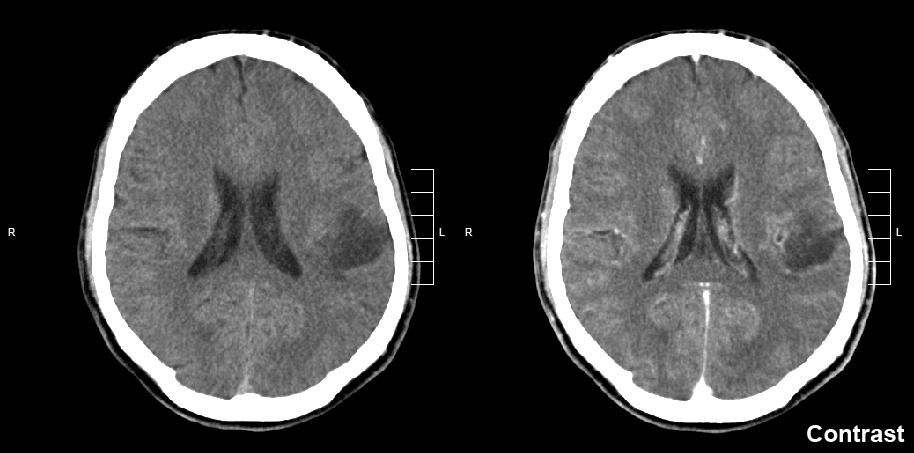

那么,原发性胶质瘤是恶性还是良性?一般来说,胶质瘤为恶性但程度有高低,胶质瘤其实就是中枢神经系统神经胶质细胞发生癌变而形成的肿瘤,故又称为神经胶质细胞肿瘤,它是中枢神经系统较常见的原发性肿瘤。胶质瘤浸润性生长的生物学特性决定了它没有良性和恶性之分,只有低度恶性和高度恶性之别。胶质瘤是发生于神经外胚层的肿瘤,故亦称神经外胚层肿瘤或神经上皮肿瘤。和多数脑子里不同的是,胶质瘤不能笼统的概括为良性或者恶性肿瘤,其恶性程度要根据患者情况而定。

国际卫生组织根据肿瘤的恶性程度不同,将胶质瘤分为Ⅰ至Ⅳ级,其中Ⅰ、Ⅱ级为低级别胶质瘤,包括毛细胞星形细胞瘤、弥漫性星形细胞瘤、少突胶质细胞瘤、少突星形细胞瘤等;Ⅲ、Ⅳ级为高级别胶质瘤,包括间变性星形细胞瘤、间变性少突胶质细胞瘤、间变性少突星形细胞瘤、胶质母细胞瘤等。